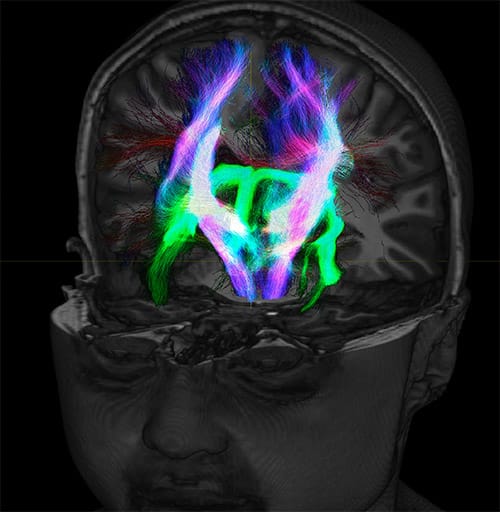

Fiber tractography of the corticospinal tract with seed region of the posterior limb of the internal capsule. Different processing based on the same data.

All images were created from the same acquisition in a child using Ingenia 3.0T CX and 32-channel dS Head coil. Diffusion data was acquired at b-values 0, 500, 1000, 2000, 3000. The use of high b-values (3000 s/mm2) effectively suppresses extra-axonal water signal and provides high angular resolution.

Fiber tracking based on CSD analysis of multishell DWI data and probabilistic tractography.

Fiber tracking from the left and right hippocampi to the fornix.

Fiber tracking from the left and right hippocampi to the fornix (green), and the corticospinal track based on a seed region of the posterior limb of the internal capsule.